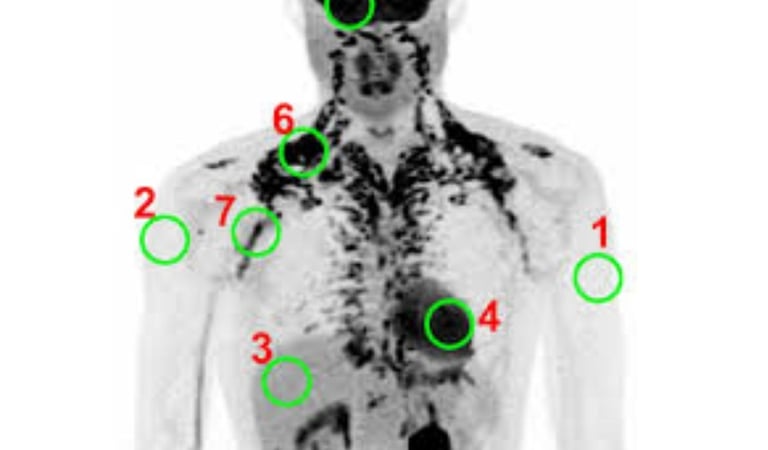

The ¹⁸F-FDG PET-CT scan has been a common method for assessing BAT.

When BAT is active, it uses up glucose, which is marked by the radioactive FDG tracer to show where the BAT is.

1. Xenon-Enhanced CT (Xe-CT): A More Accurate Option

Xenon-Enhanced CT is a big jump forward.

Recent studies that compared it directly with PET/CT suggest that Xe-CT could be more accurate for measuring BAT.

Since BAT has many blood vessels, it absorbs inhaled xenon gas rapidly.

This provides a strong signal that measures how well the tissue is functioning.